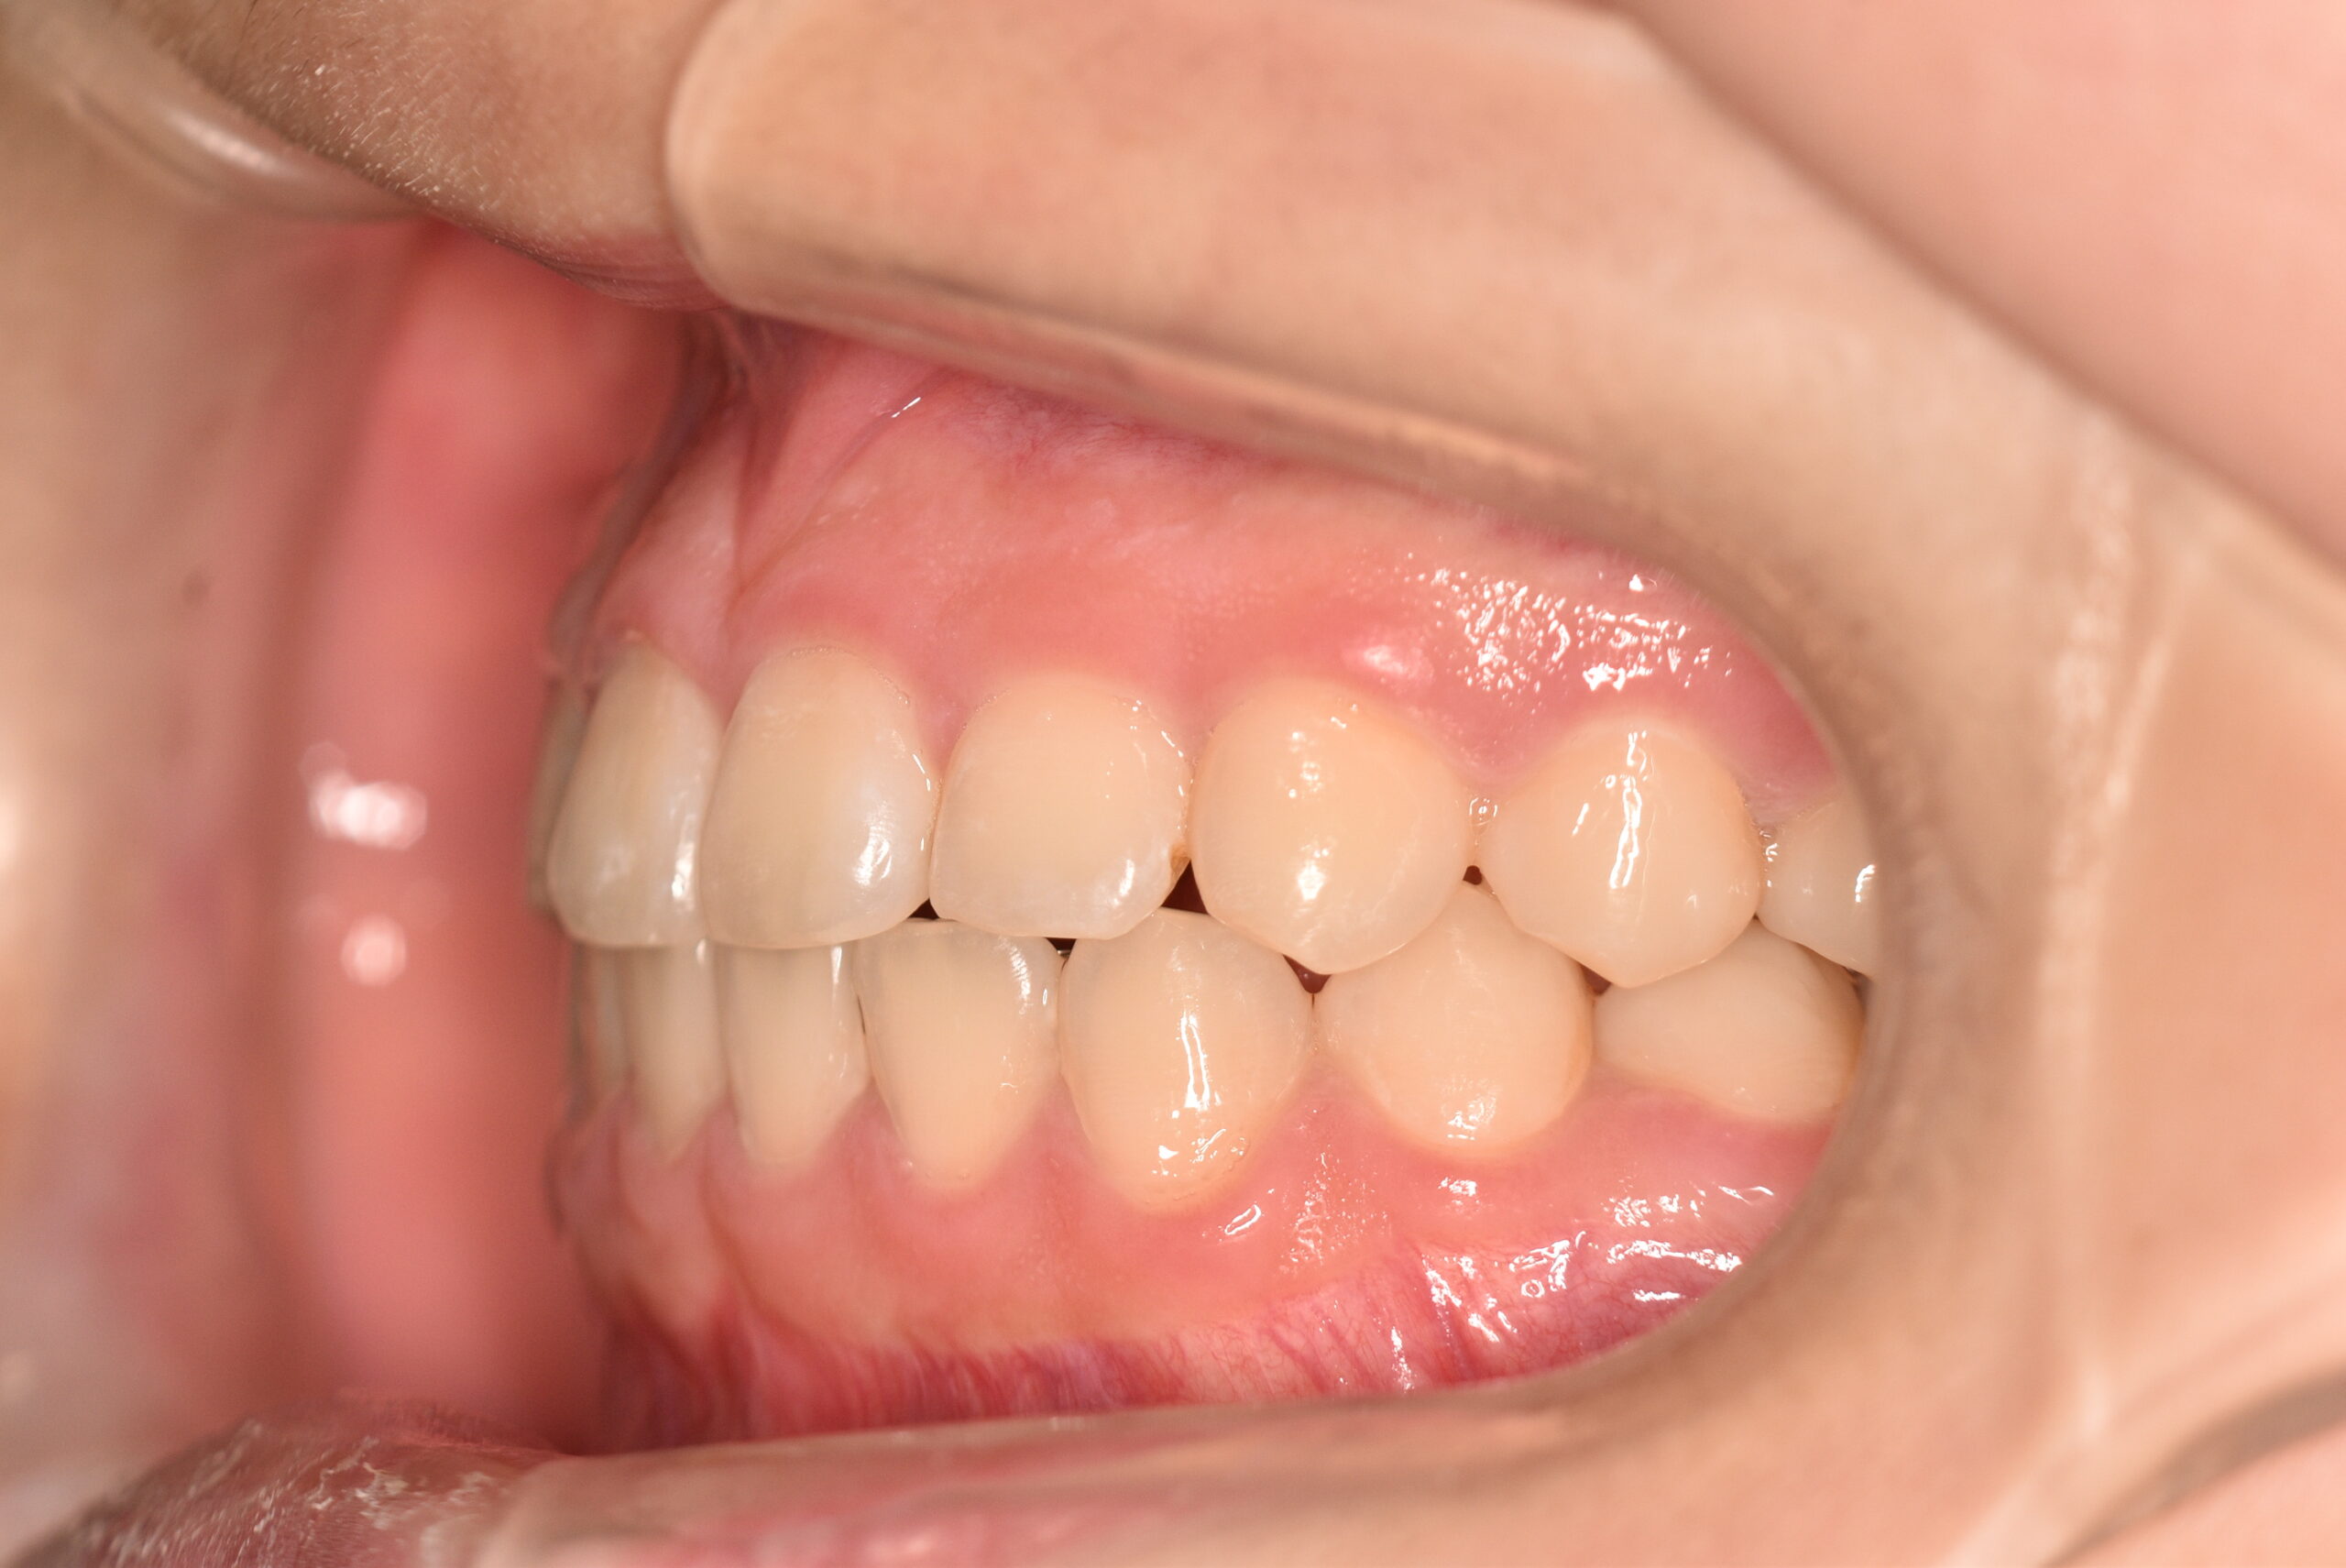

反対咬合(非抜歯)[2345]

初診時

動的治療終了時

年齢

8歳8ヶ月 性 別 女性

治療期間 4年3ヶ月 費 用 矯正施術料:800,000円 調整料:4,000円/月

治療内容の詳細 初診時8歳の女性で、下顎が出ていると歯科医からの指摘を気にされ来院されました。

検査の結果、反対咬合を伴うアングルⅢ級不正咬合と診断しました。

治療としては、初期段階の治療として、リンガルアーチを使用して上顎前歯部を前方へ移動させ、反対咬合の改善を行いました。また、機能的矯正装置で鼻呼吸の獲得と舌の位置や口唇の閉鎖といった筋機能習癖の改善を行いました。

永久歯列に交換後、非抜歯の上、セルフライゲーションブラケット装置(デーモンシステム)で歯の配列を行いました。

治療期間は、4年3ヶ月でした。